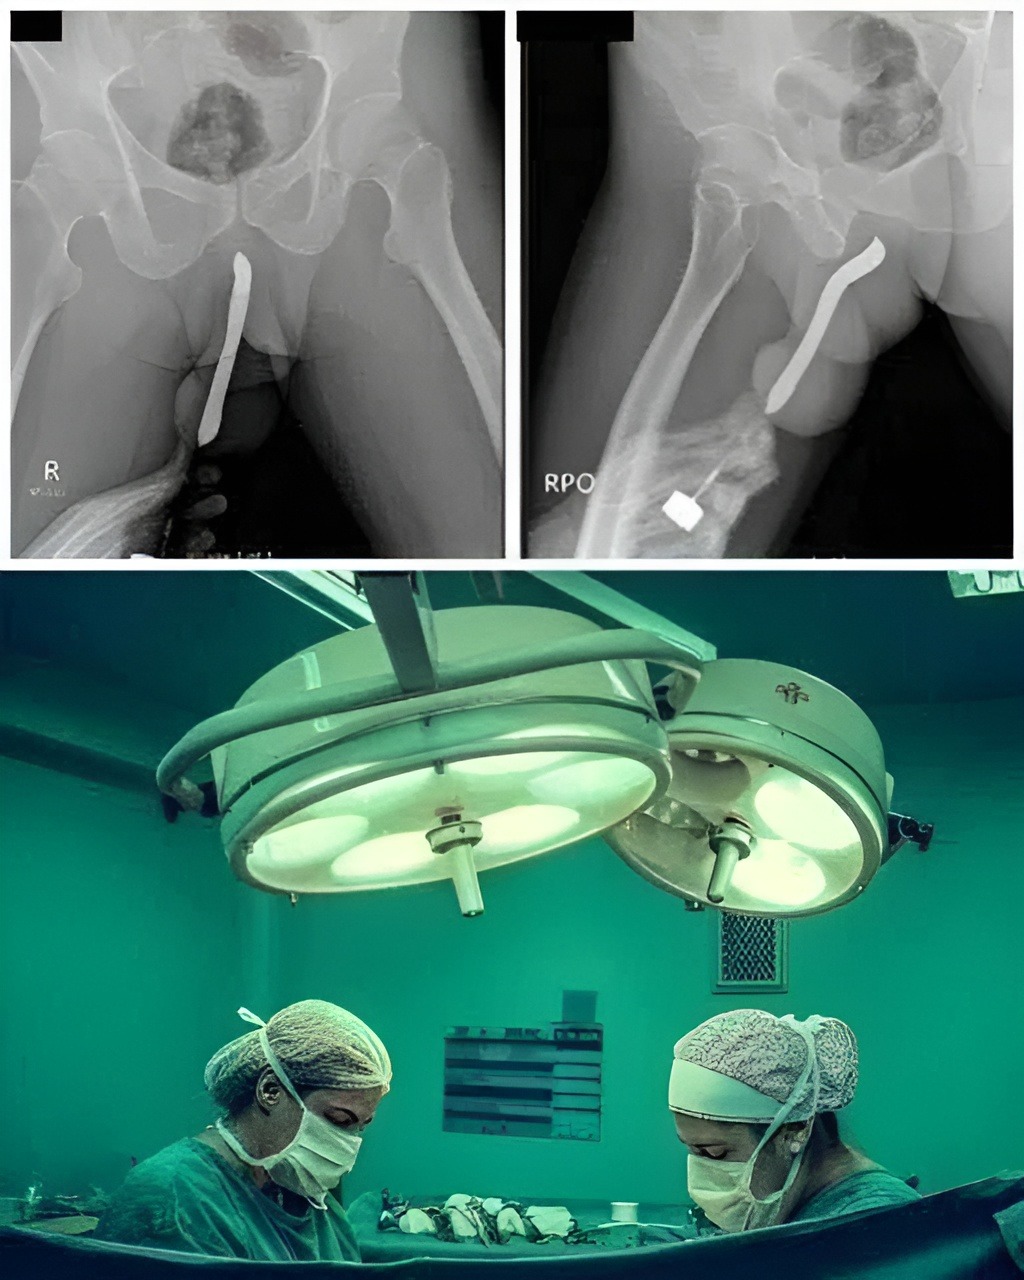

The X-ray That Explained Everything

Once she arrived at the emergency room, doctors began running tests. Because the cause of her pain was unclear, they ordered a scan to rule out internal bleeding or abdominal complications. What they found instead was the household tool lodged deeper inside her body than she realized — not due to intentional usage, but due to the angle, force, and the completely accidental way it had slipped.

The medical team immediately prepared for a controlled procedure to remove the object safely, as improper handling could worsen the injury. Fortunately, they were able to retrieve it without major surgical intervention, and there were no long-term complications.

However, the situation was serious enough that the hospital later issued a public safety notice urging people to be more cautious when handling long or pointed household tools — especially in tight spaces or when used near the body.